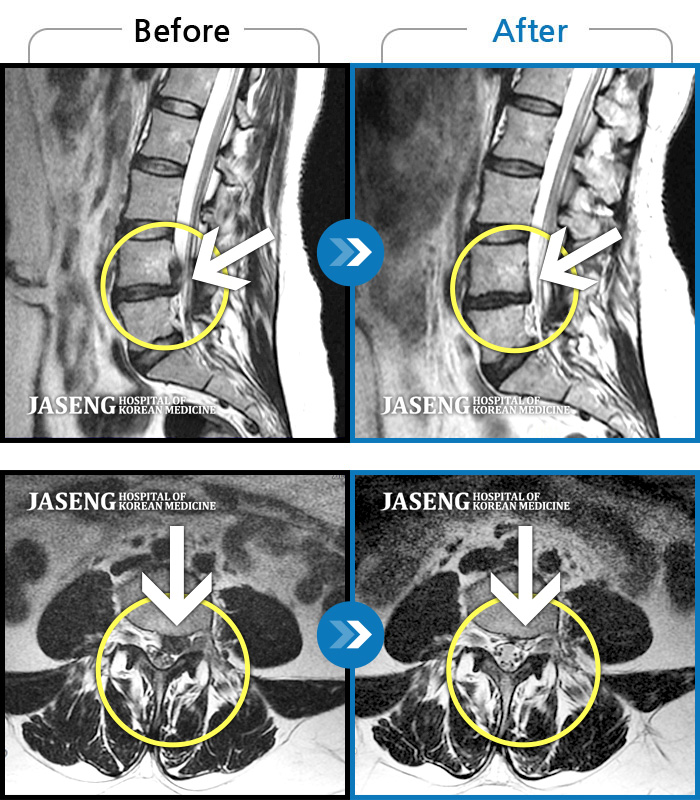

허리디스크

부천 · 최요섭

허리굽히는 동작을 한 후 우측 골반통증 및 우측 하지외측 저림, 근력저하가 있었다.

촬영시기

2023.06.15 ~ 2024.03.29

2024.04.05

조회수 433